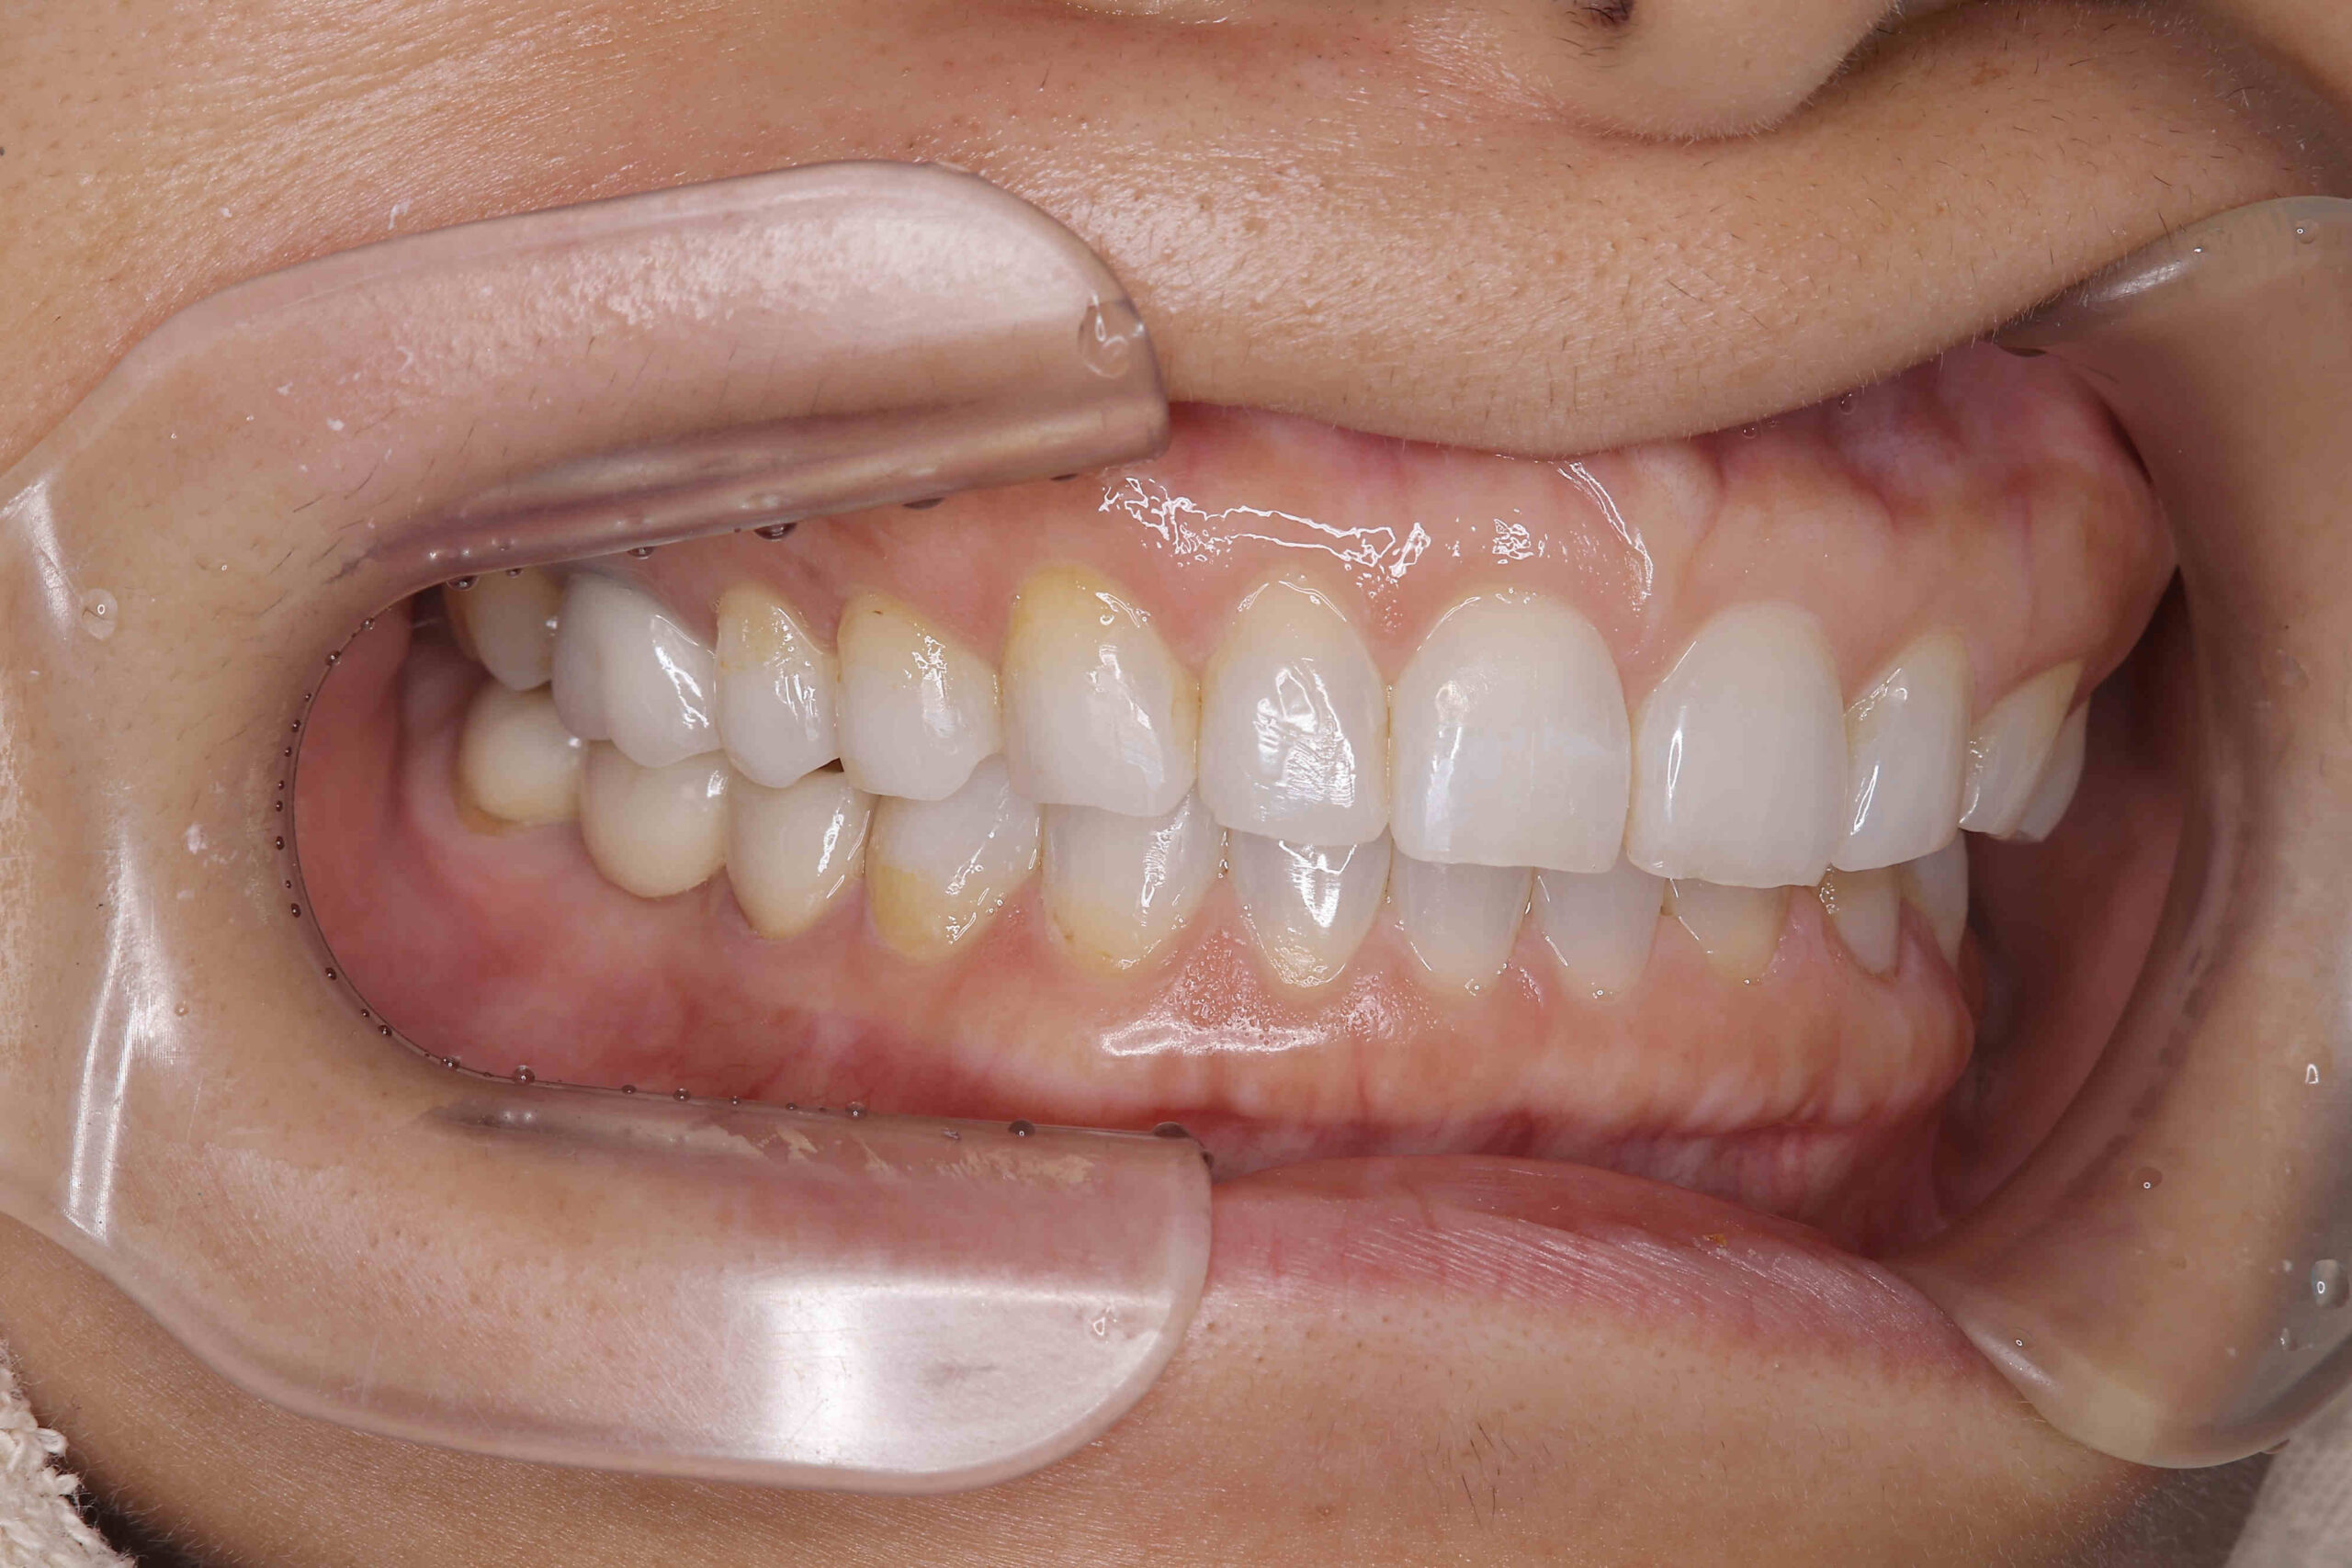

• 治療前

治療後

元々咬む筋力や食いしばり・歯ぎしりが非常に強く、『フレアーアウト』(前歯の歯並びが前方に放射状に倒れていく現象)によって「出っ歯」や「すきっ歯」の状態になっていました。

今回はご希望のマウスピース矯正で、食いしばりや歯ぎしりによる歯の破折やすり減りを予防しながら、歯と歯の隙間が広がって傾斜した前歯を元の位置に戻しました。

ホワイトニングも同時進行で施術し、白く輝く歯になりました。

元々入っていた臼歯のブリッジは治療せず、そのままの位置で矯正を行うことを希望されたため、正中(上顎と下顎の中心線)を合わせることは難しいですが、美しい歯列と口元へ仕上がりました!